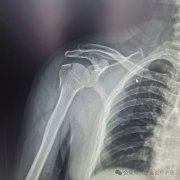

骨折的启示 一一写在手臂骨折百天

3月份时不慎跌倒,拍片后确诊是右臂肱骨近端大结节骨折(医学专用名)。这...